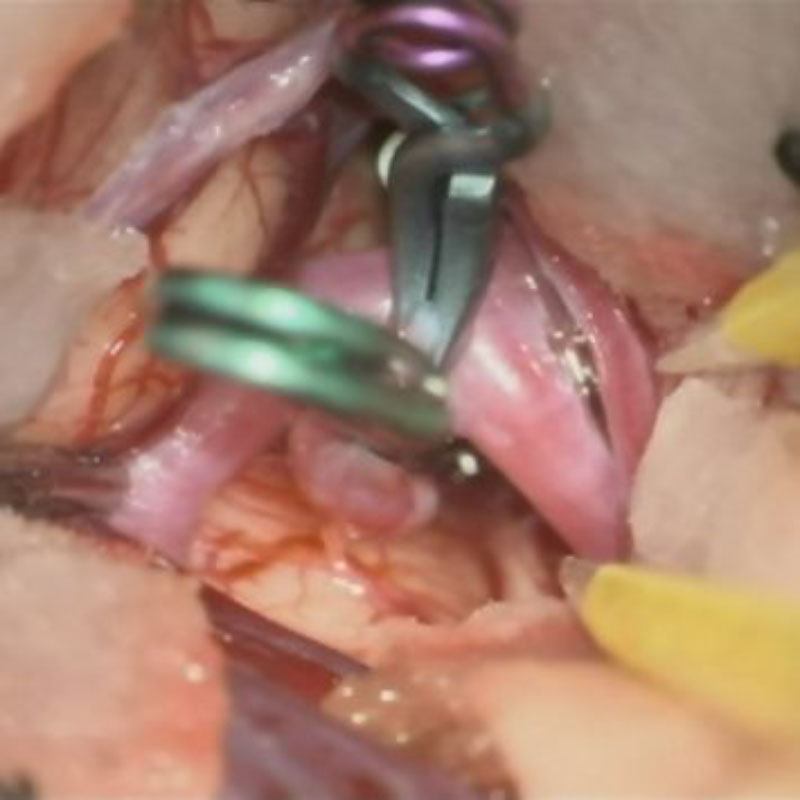

クリップ前